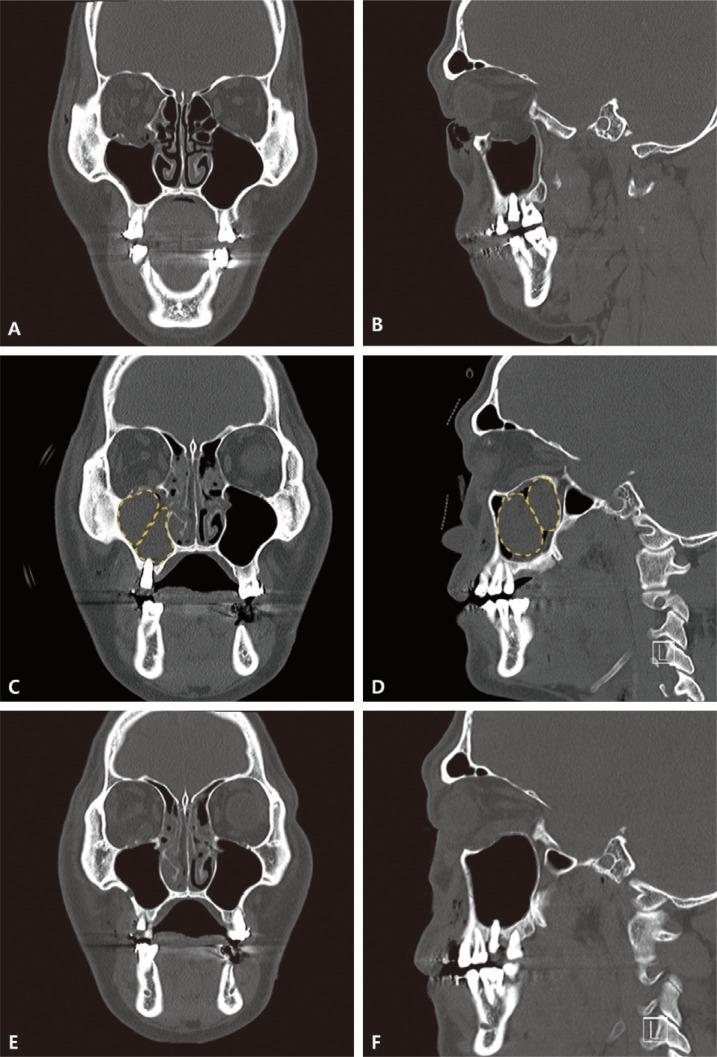

The reduction of orbital blowout fracture primarily aims to normalize the extra-ocular movement by returning the herniated orbital soft tissue into the original position, and to prevent enophthalmos by normalizing the orbital cavity volume. We introduce a balloon catheter-assisted orbital floor reduction technique.

A retrospective review was performed for all patients with orbital floor fracture who underwent the technique described in the main body of this text. Medical records were reviewed for demographic data, clinical presentation and course, degree of enophthalmos, intraorbital volume on computed tomography scan, and postoperative outcomes. The enophthalmos and intraorbital volume of the injured site were compared to the uninjured eye and orbit.

The review identified 14 patients (11 male, 3 female). The mean preoperative difference in en-exopthalmos was 2.13 mm, while the mean orbital volume was 116%. The mean postoperative difference in en-exophthalmos had improved to 0.61 mm with a mean orbital volume of 101.85%. At the time of catheter removal at 10 days, three patients experienced diplopia (n=1), extra-ocular movement disorder (1), or enophthalmos (1). All of these had resolved by the 6-month follow-up visit.

Balloon catheter-assisted reduction of the orbital floor fractures was associated with improvements in intraorbital volume and enopthalmos in the 14 patients. Notable complications included diplopia, enophthalmos, and limited extra-ocular movement, all of which were transient in the early postoperative period and had resolved by 6-month follow up.